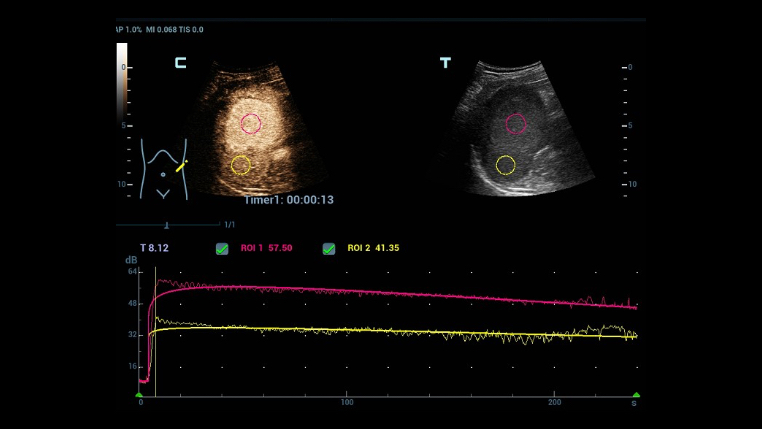

HD Scope: By processing channel data retrospectively, HD Scope enables tissue-specific enhancement with improved detailed information and image contrast on specific region of interest.

As ZST+ captures and stores the complete acoustic raw data set. Total Recall Imaging allows system to do retrospective processing on channel data and also permits users to modify numerous imaging parameters on stored images to maximize clinical output.